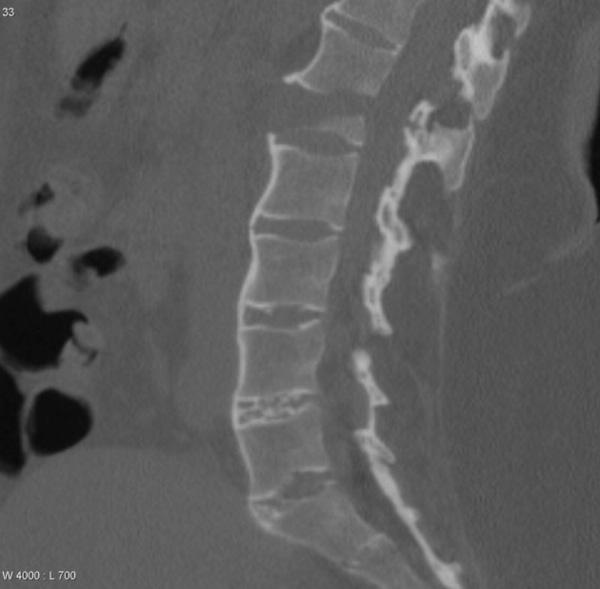

Chụp cắt lớp vi tính (CT) sử dụng kết hợp tia X và công nghệ máy vi tính để tạo ra hình ảnh chi tiết về cấu trúc bên trong cơ thể. Khác với chụp X-quang chỉ tạo ra hình ảnh hai chiều, chụp CT khớp có thể chụp ảnh không chỉ cấu trúc xương mà còn cả các mô mềm như gân, dây chằng, cơ và mạch máu. Điều này cho phép phân tích toàn diện tình trạng của khớp đang được kiểm tra, bao gồm cả tổn thương sụn.

Trong quá trình chụp CT, một chùm tia X hẹp được phát ra từ máy quét và di chuyển xoay tròn xung quanh cơ thể. Các cảm biến sẽ ghi nhận lượng tia X được hấp thụ bởi các mô khác nhau, từ đó tạo ra hình ảnh chi tiết về cấu trúc bên trong. Thông tin này sau đó được xử lý bởi máy vi tính để tạo ra hình ảnh hai chiều hoặc ba chiều, giúp bác sĩ có cái nhìn trực quan về cấu trúc khớp.